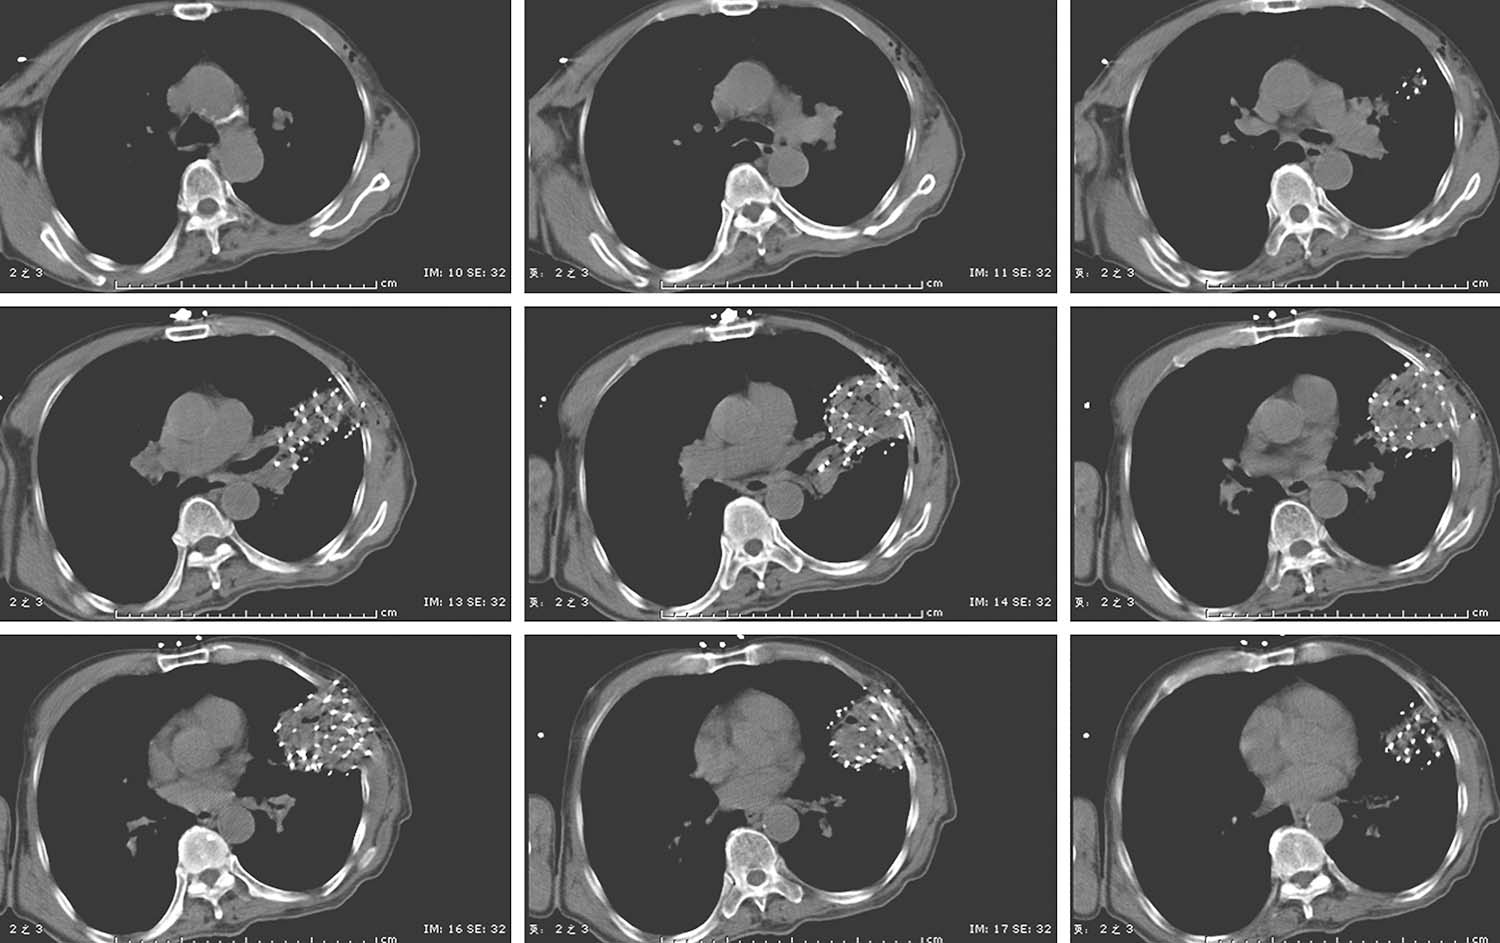

所有患者术前3天行强化CT扫描,依据病灶部位采取仰卧、俯卧、侧卧等体位,真空负压垫固定。拷贝DICOM格式CT图像传输至近距离TPS设计术前计划,临床医生与物理师共同勾画肿瘤靶区体积(GTV)和邻近危及器官(OAR),设定处方剂量和粒子活度,根据病灶位置及与周围重要脏器的关系,设计进针路线,模拟粒子空间分布,确定粒子间距及排布方式,计算粒子数目,计算GTV及OAR的照射剂量,得出剂量体积直方图(DVH)及逐层等剂量分布图。

患者取与术前CT扫描相同体位,真空负压垫固定体位,防止穿刺过程中因体位变动给穿刺带来的不利影响。将导航支架与CT碳纤维床板相连接,以0.5cm层厚扫描,选取病灶中心层面,将一个预定进针点在皮肤表面做出大十字标记,消毒、铺巾、局麻,安装模板,用激光灯校准模板,使激光灯的 x 轴和 y 轴投影与模板表面的标记线相重合,利用数字化角度仪或者水平仪调整模板的角度和方向,使模板在 y 轴方向的角度为零,调整 x 轴方向的角度,与术前计划保持一致。选择病灶中心层面,参考术前计划,将数根穿刺针抵达皮肤表面,扫描观察针尾走行方向,再次校准模板,然后测量进针的深度,完成该层面的进针,如果是肺等移动度较大的脏器,可以先插入2~3根固定针,将病灶与模板迅速“绑定”(图4-3-1),然后再依次完成其他层面的进针,如果遇到坚韧骨骼遮挡,使用捻针或骨钻打孔技术破骨插植,待完成所有层面的进针以后再植入粒子。

图4-3-1 进针过程

例1 患者男性,72岁,左肺鳞癌侵犯胸壁并同侧肺门淋巴结转移,T4N1M0。2018年1月16日行共面模板引导放射性粒子植入术(图4-3-2~图4-3-7)。

例2 女性,76岁,左肺周围型腺癌,T4N0M0,2017年10月12日行共面模板引导放射性粒子植入术(图4-3-8~图4-3-13)。